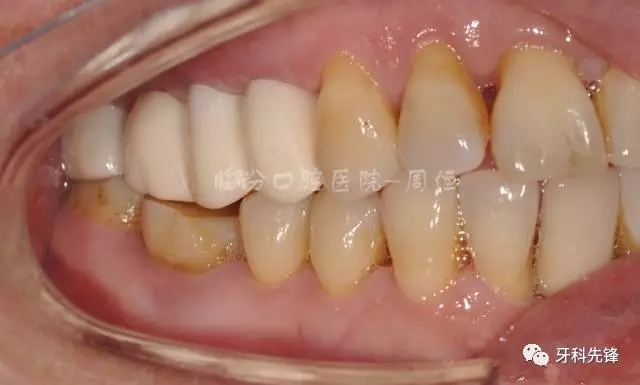

圖2  術(shù)前側(cè)位咬頜照

640.webp (3).jpg

圖5拆除原修復(fù)體側(cè)位咬合照

640.webp (6).jpg